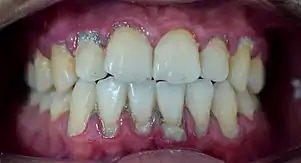

La parodontie est la partie de la dentisterie qui est spécialisée dans le traitement du parodonte, c'est-à-dire les tissus de soutien de la dent : gencive, tissu osseux, cément et ligament parodontal.

Le parodontiste prévient, diagnostique et traite les gingivites et les parodontites, ainsi que leurs séquelles. Il assure également le remplacement des dents absentes par les techniques de greffes osseuses et de chirurgie implantaire. Il traite aussi les récessions gingivales par les techniques de chirurgie plastique parodontale de recouvrement radiculaire.